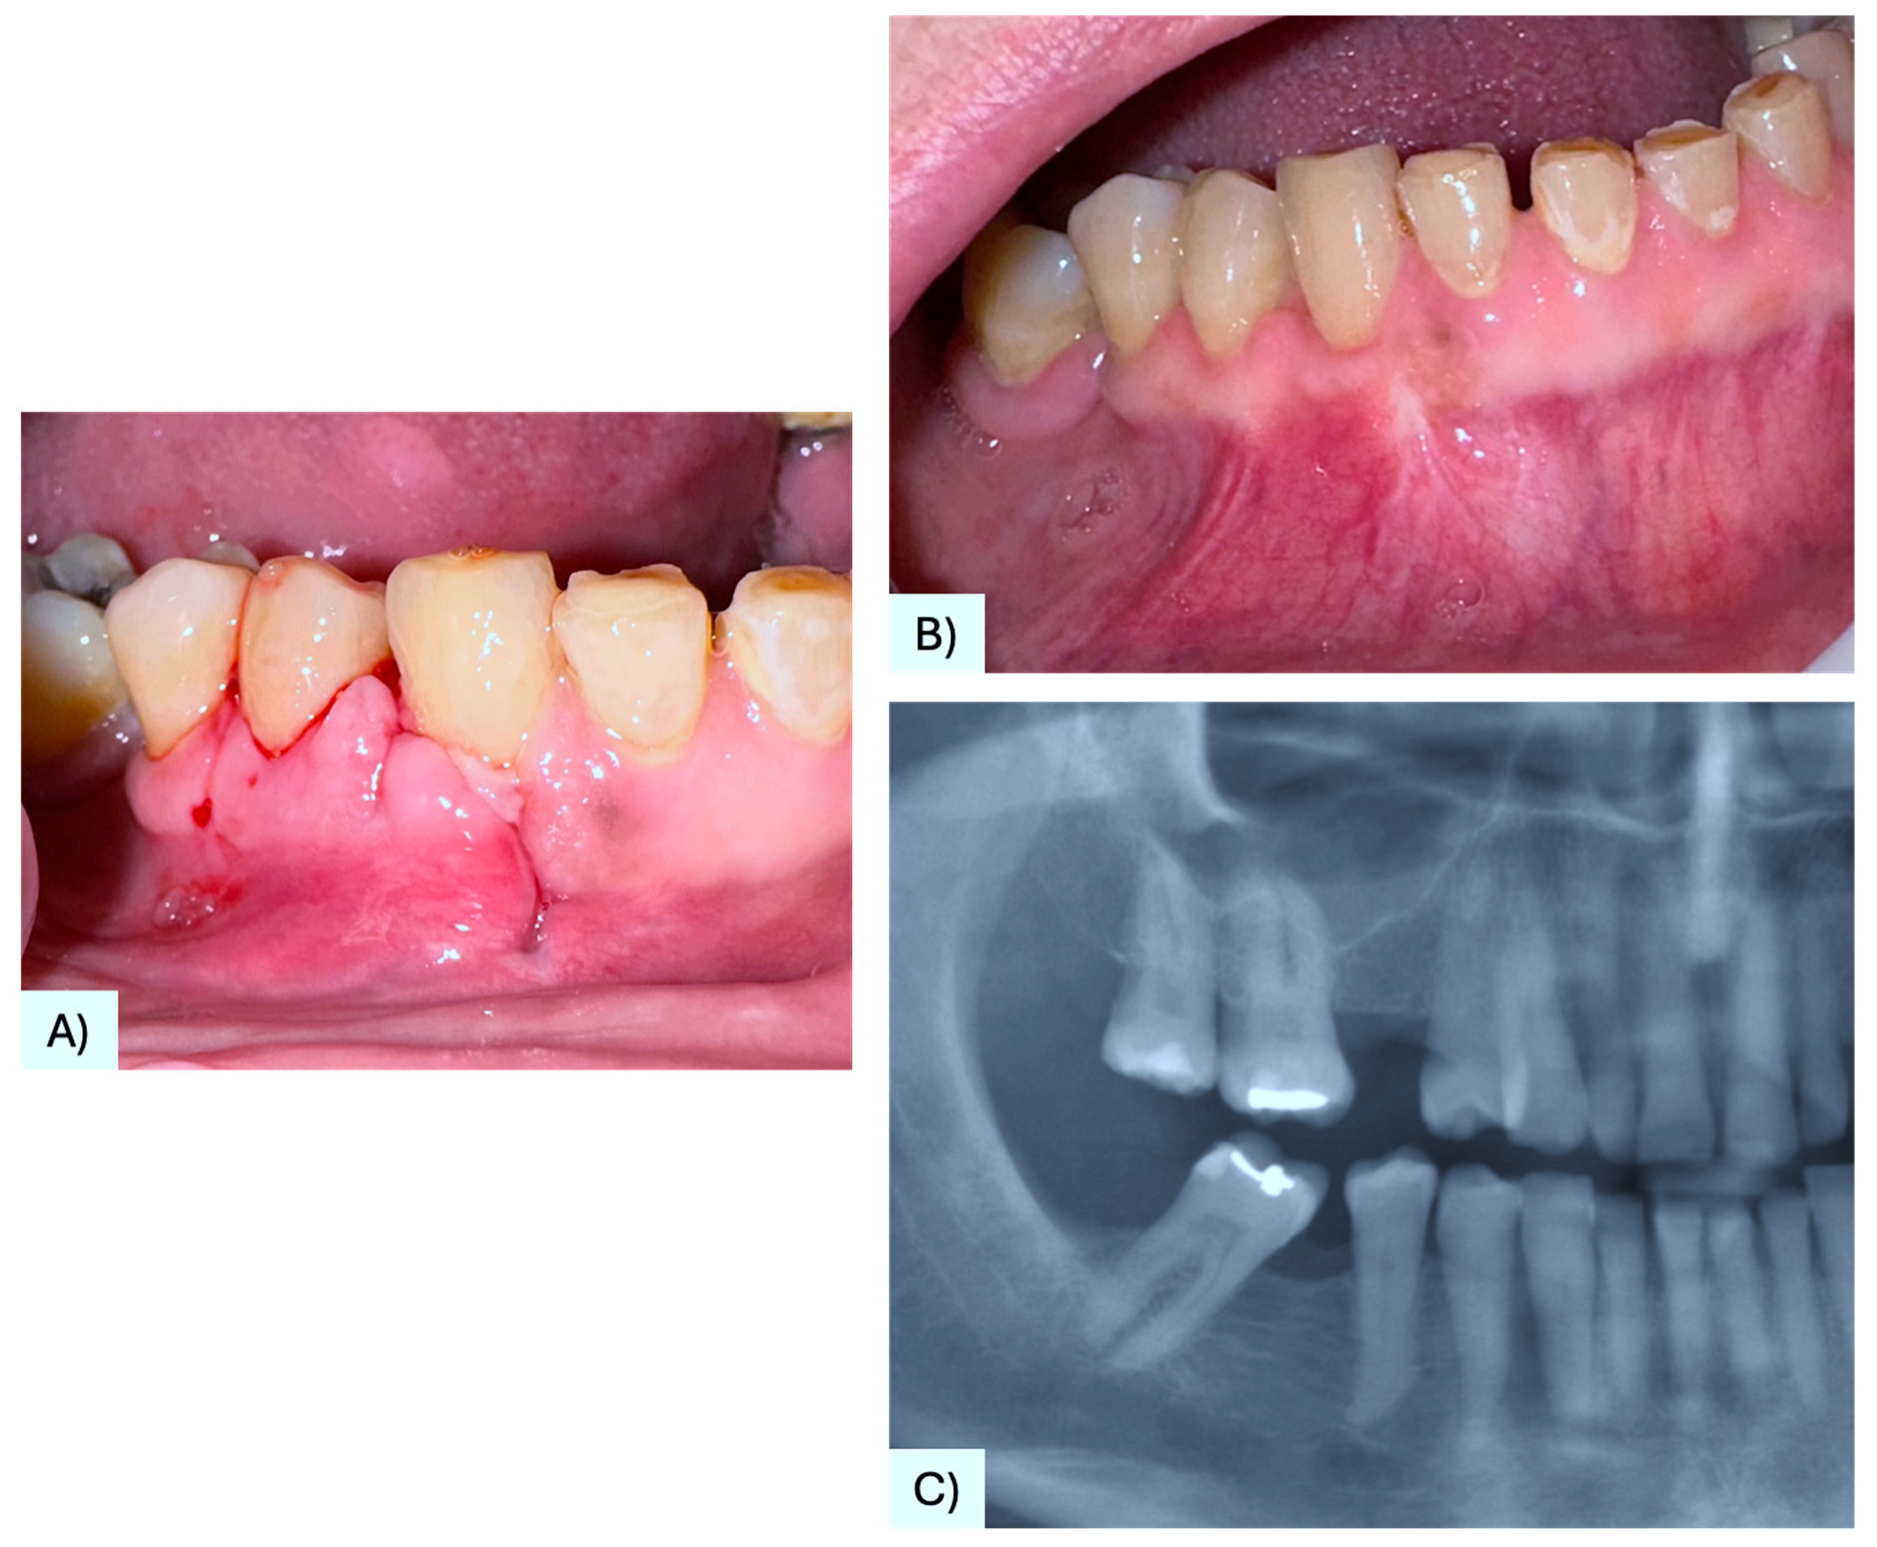

3.1. Case Presentation

| 37 | Present case | 68 F | Maxilla, between #4.3, #4.4 | Asymptomatic nodule | 15 mm | Radiolucency with a defined margin area | Alveolar bone resorption | Excisional biopsy, curettage | No recurrence at 6 months follow-up | 2025 |